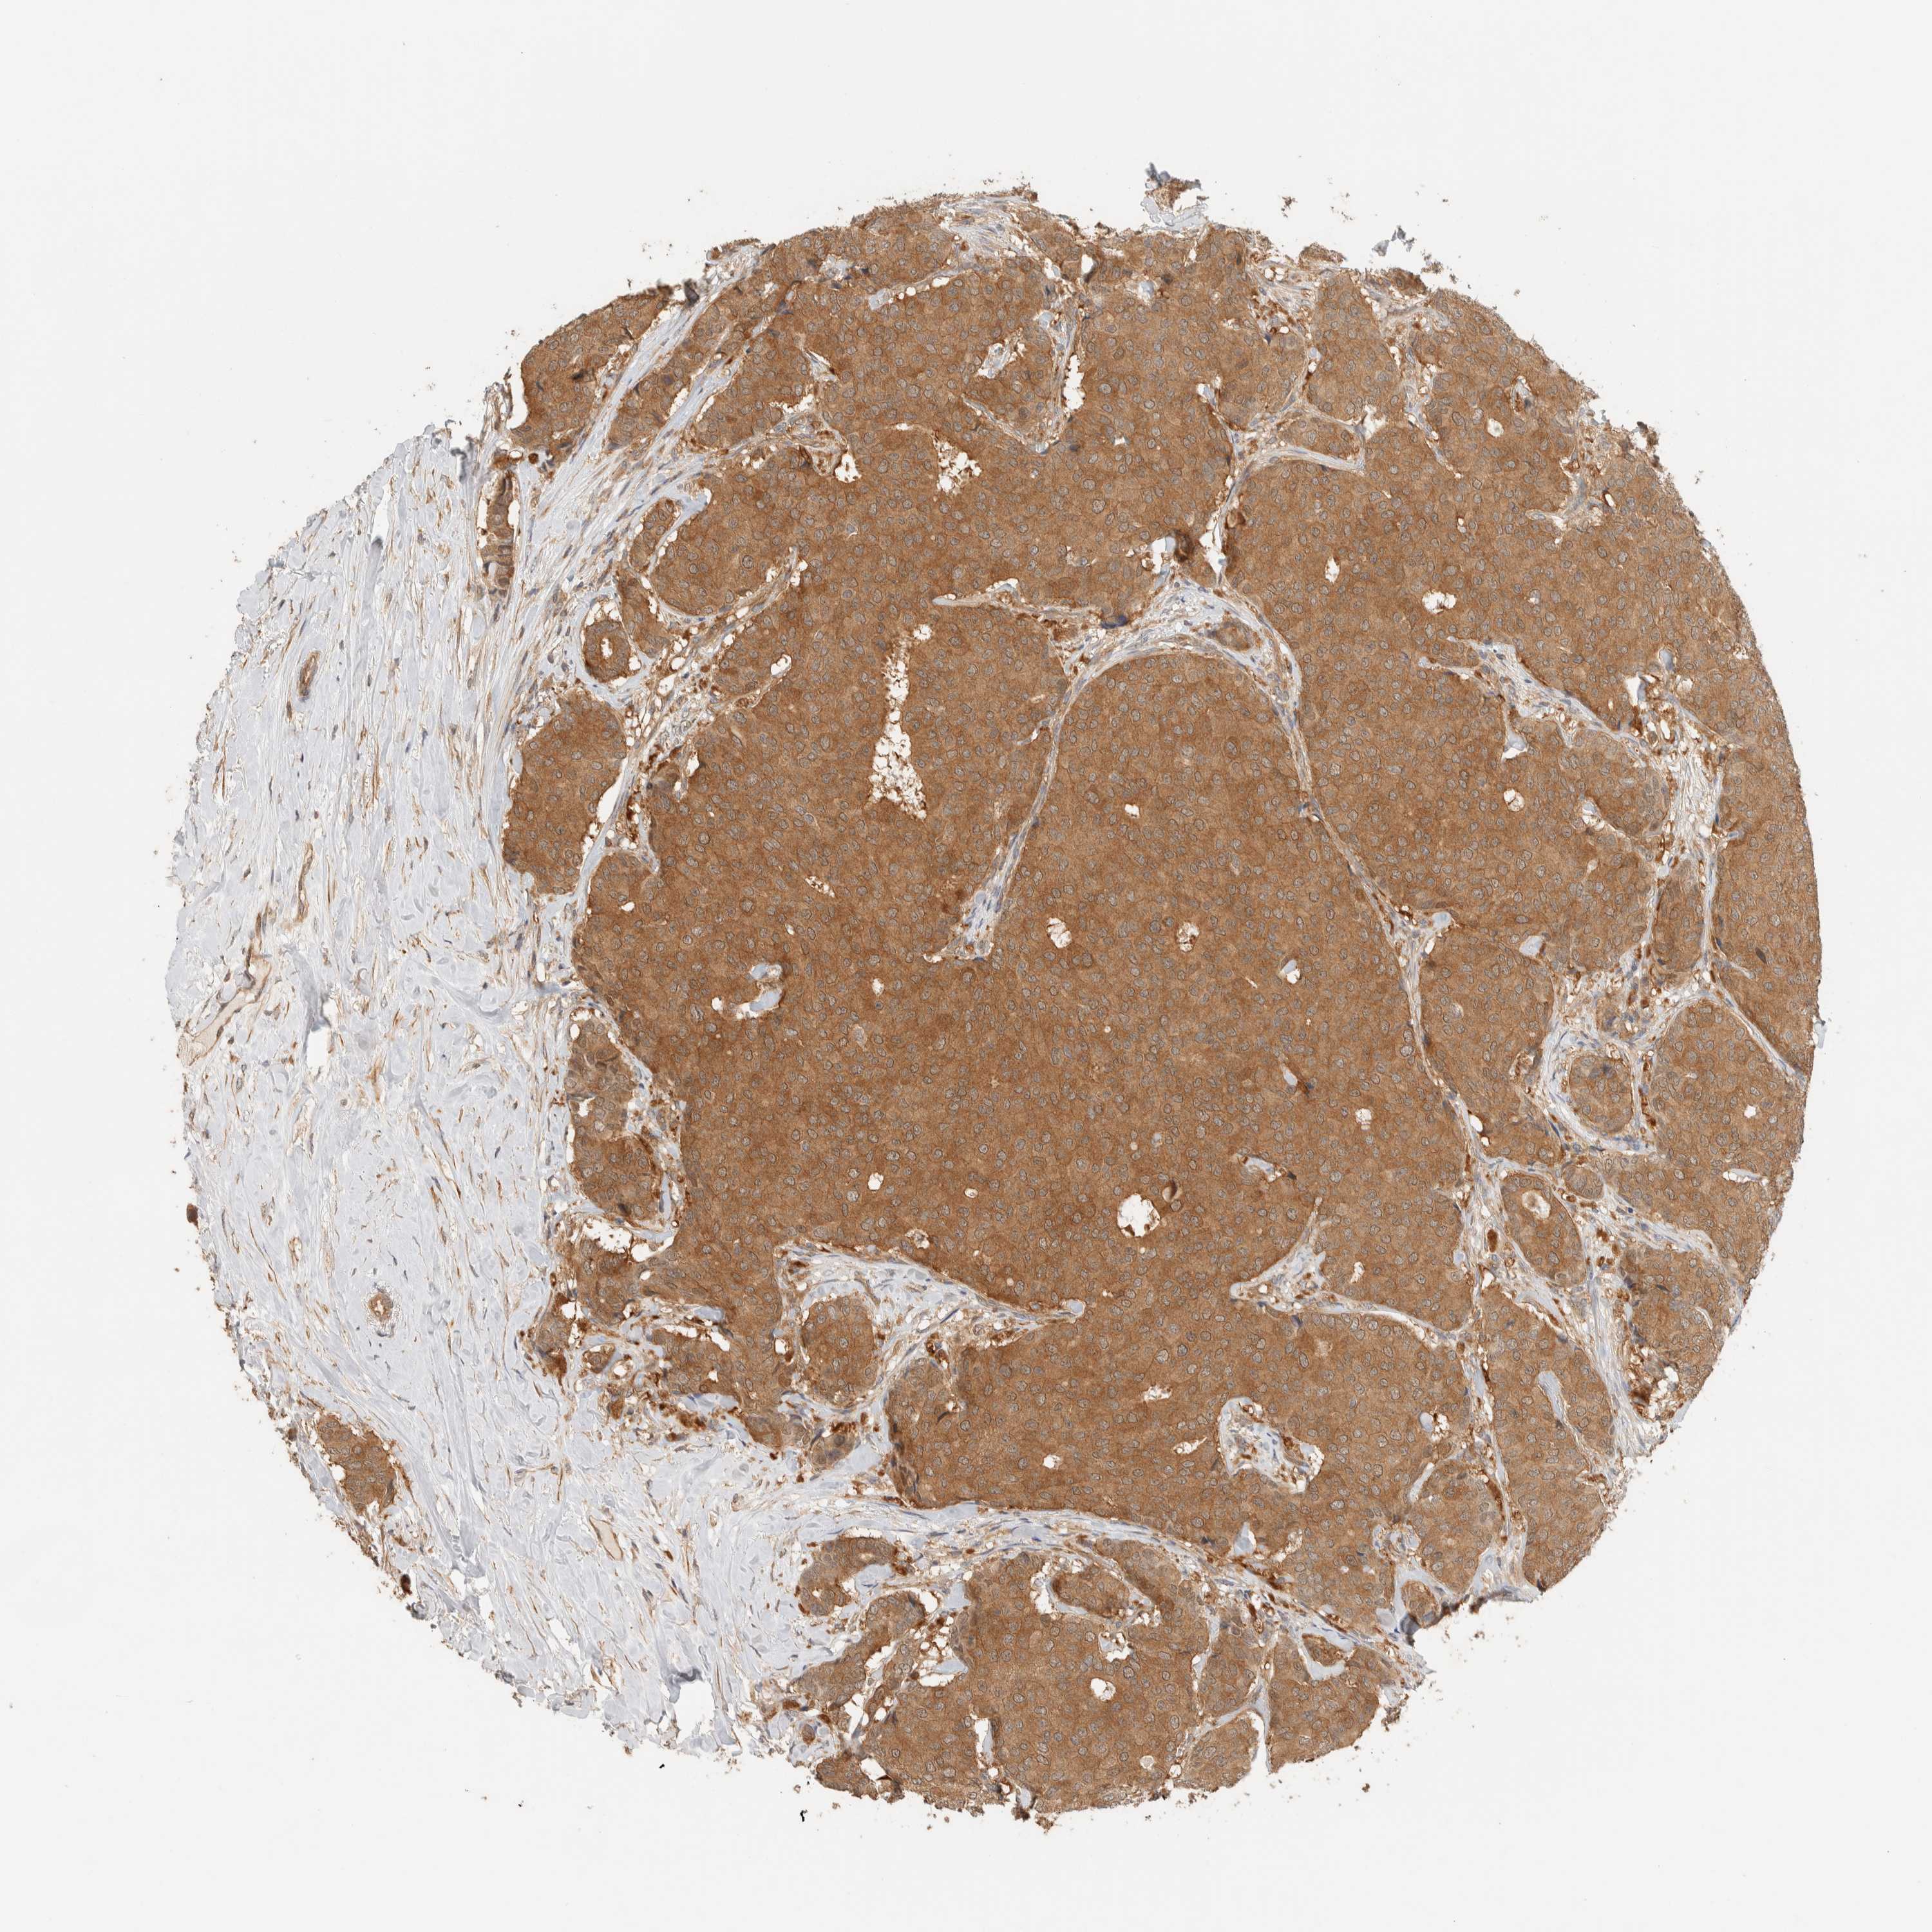

BRCA TCGA BRCA VALIDATION PROTEIN EXPRESSION